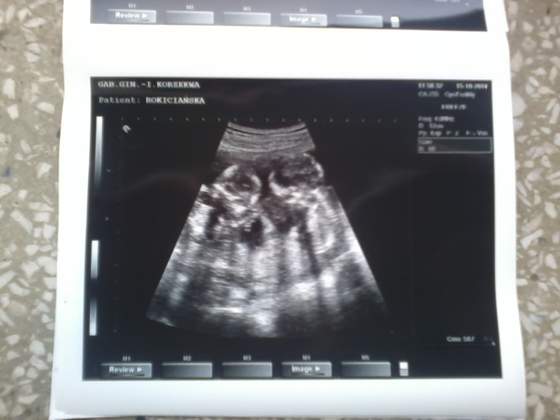

A to moje Motylki :-) przepraszam za kiepską jakość:zawstydzona/y:

14tc razem.jpg14tc ser1.jpg14tc ser2.jpg